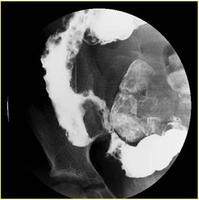

肠道钡餐造影能了解末端回肠或其他小肠的病变和范围。其表现有胃肠道的炎性病变,如裂隙状溃疡、卵石征、假息肉、单发或多发性狭窄、痰管形成等,病变呈节段性分布。钡剂灌肠有助于结肠病变的诊断,气钡双重造影可提高诊断率。X线腹部平片可见肠拌扩张和肠外块影。腹部CT,检查对确定是否有增厚且相互分隔的肠袢,而且与腹腔内脓肿进行鉴别诊断有一定价值。